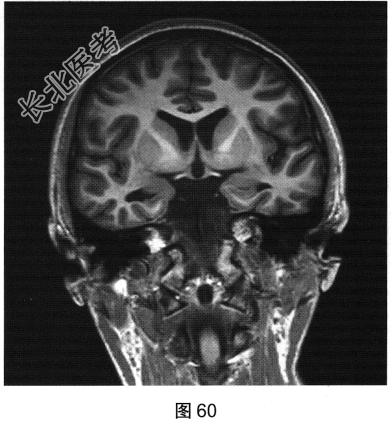

- 多项选择题2.[提示]患者行颅脑MRI检查,见图60、图61。MR检查可见哪些阳性影像学表现( )

A、右侧海马形态萎缩

B、右侧海马T2FLAIR信号增高

C、左侧颞叶皮质萎缩,脑沟增宽

E、左侧海马T2FLAIR信号增高

F、左侧海马形态萎缩

G、右侧颞叶皮质萎缩,脑沟增宽